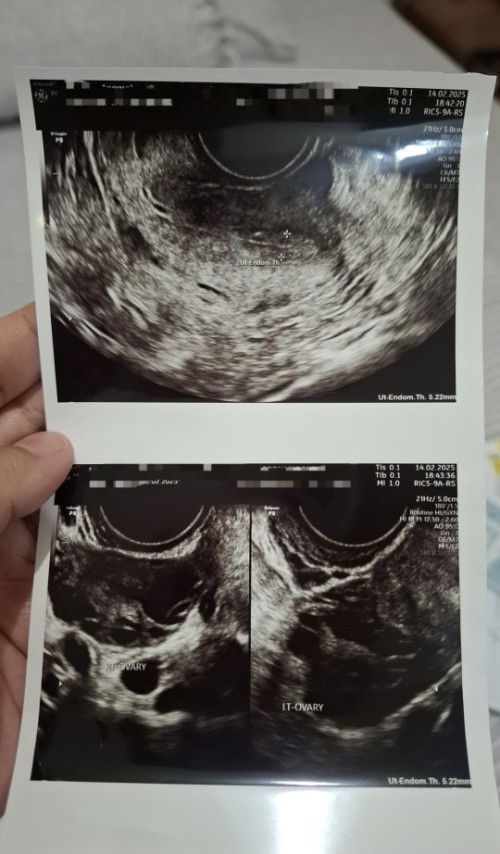

untuk perbandingan, ini contoh usg PCOS aku jadi bun sel telurnya terlihat kecil-kecil dan banyak, tidak ada yang matang padahal masa subur. bisa dicek lebih jelas lewat usg transvaginal. biasanya kalau usg perut gak terlalu nampak. semoga membantu yaa 🫶🏻